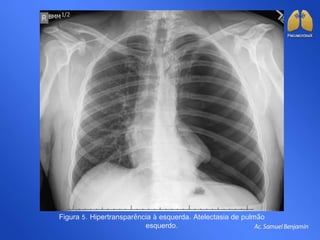

Figura 5. Hipertransparência à esquerda. Atelectasia de pulmão

esquerdo.

Figura 5. Hipertransparênciaà esquerda. Atelectasia de pulmão esquerdo.